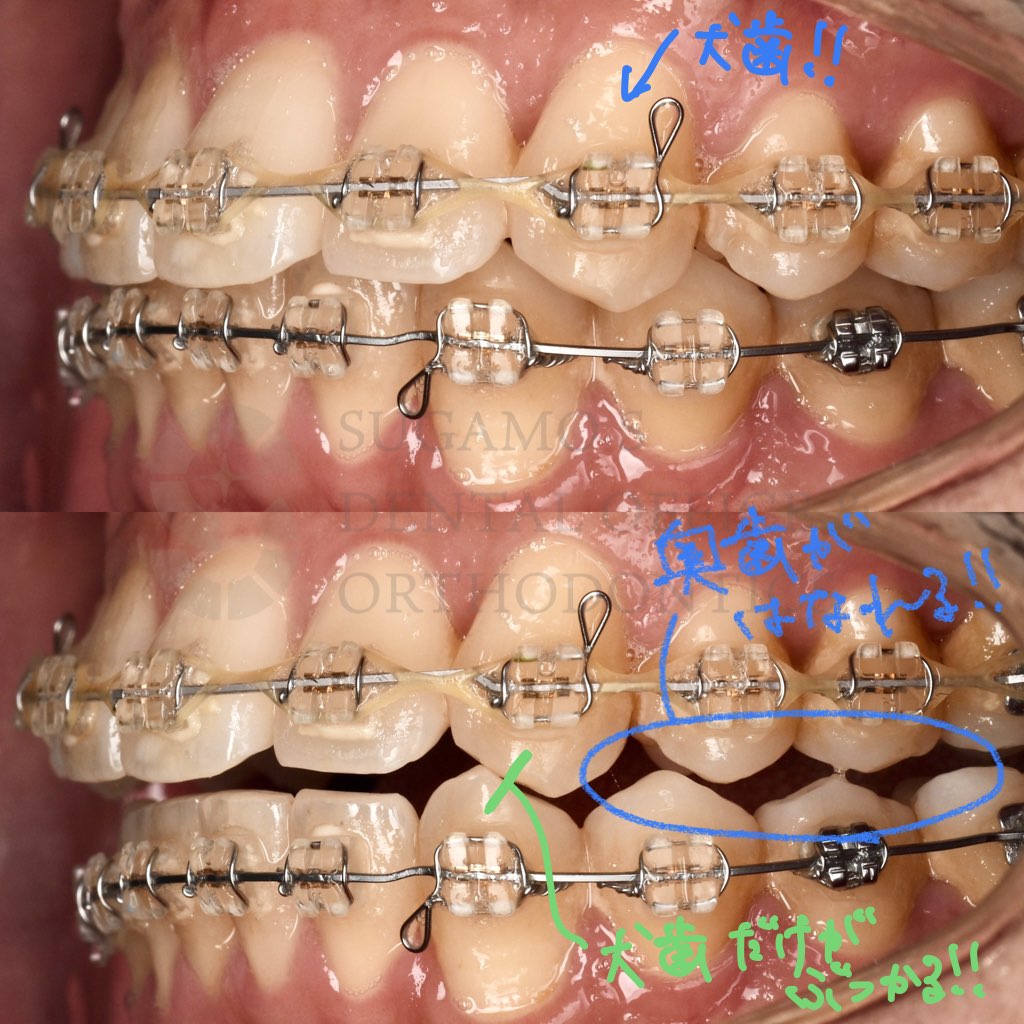

さらに犬歯誘導が達成できている咬み合わせは、

かみ合わせた状態から下顎を左右に動かしたとき、

犬歯だけがぶつかり、他の歯がぶつからない状態になるわけです。

つまり、顎を横に動かしたとき、

一番耐久性のある犬歯がぶつかってくれることで他の歯の負担を軽減しているんです。

カチッと噛んでから横にずらして歯軋りのような動きをしたときに犬歯だけがぶつかり、奥歯が離れていくかみ合わせのこと。